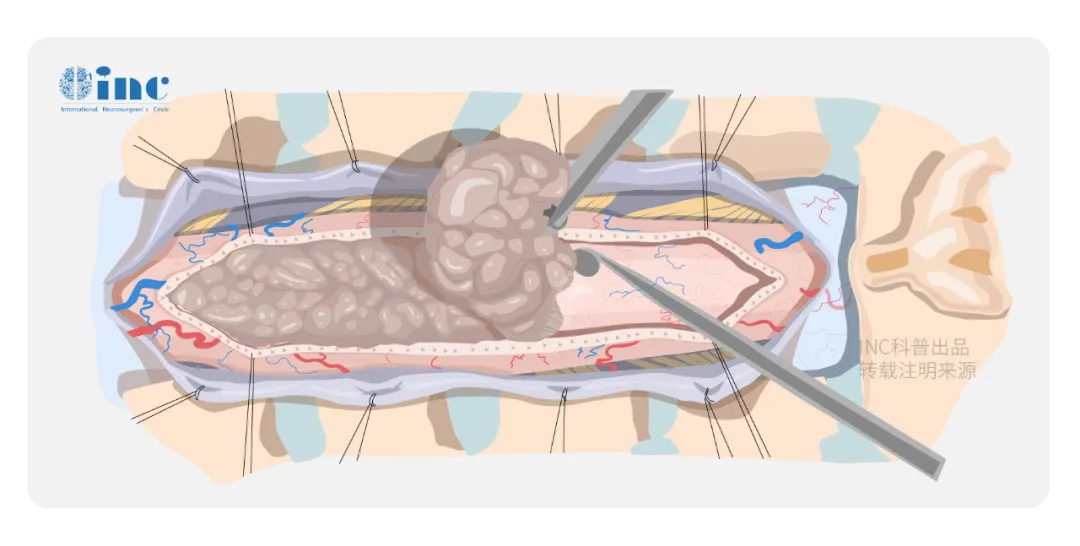

對于大多數(shù)脊髓腫瘤,首選治療方法是手術。手術在神經(jīng)外科高清顯微鏡下進行,視野放大數(shù)倍,脊髓和其表面血管結構清晰可見,同時在術中實時電生理監(jiān)測的保護下,縱行切開脊髓,用顯微器械小心分離并切除腫瘤。

手術最主要的目的是解除脊髓或神經(jīng)根受壓,減輕神經(jīng)性疼痛,幫助患者恢復功能,改善生活質量。在保護脊髓功能的前提下,安全分離腫瘤-脊髓界面盡量全切腫瘤。